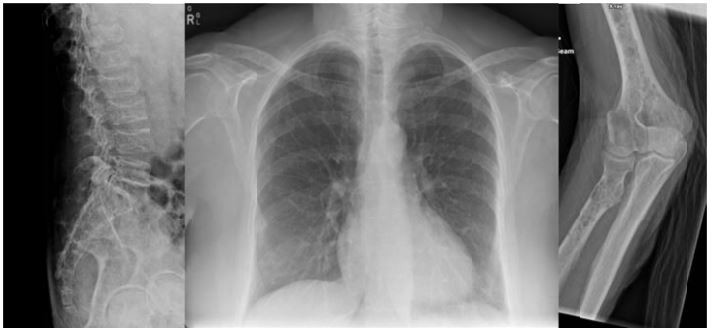

Homem, 76 anos, hospitalizado por piora do estado geral e do estado geral e queixando-se de dor em membro superior esquerdo, com limitação dolorosa, há uma semana. Relata história de lombalgia há três meses e melena há um mês. Exame físico: regular estado geral, desidrato +/4, descorado +++/4, afebril; PA 110/70 mmHg; FC 90 bpm. Addome escavado, sem visceromegalias, restante do eame segmentar normal. Dor à palpação de coluna lombar, contratura de musculatura paravertebral.

Exames laboratoriais: hemoglobina 7,2 g/dL; hematócrito 23%; leucócitos 8.200/mm³; plaquetas 39.000-mm³; ureia 87 mg/dL; creatinina 2,2 mg/dL; sódio 138 mEq/L; potássio 4,2 mEq/L; cálcio 10,3 mg/dL; THS 1,32 mU/L; ácido úrico 11,9 mg/dL.

Radiograma:

A hipótese diagnóstica é: